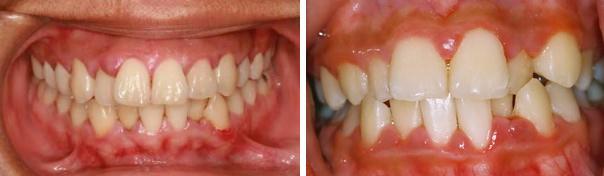

Гингивит: фото до и после

Если был диагностирован острый гингивит, все неприятные ощущения в области десен должны исчезнуть. После лечения хронического гингивита десны возвращаются к нормальной величине и перестают кровоточить, пародонтальные карманы исчезают. При грамотном лечении и удовлетворительной гигиене рецидивы заболевания отсутствуют в течение нескольких лет.